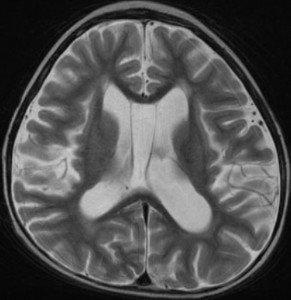

多房性白質壊死 multicystic white matter malacia

放射線により脳の髄鞘を形成する乏突起膠細胞 オリゴデンドロサイトoligodendrocyte (乏突起膠細胞)が障害を受け,脱髄 demyelinaiton が生じて白質脳症となります。上記の例はその病理像を反映するMRI所見です。

脳微小血管内皮細胞の放射線障害によって白質が小さな虚血性梗塞となり,白質壊死 white matter necrosisという重い白質脳症もあります。この場合は画像で脳の内部に穴の開いたような像(軟化巣)がみられます。上の画像は,35グレイの全脳照射を受けた5歳の子どものものです。左側が鞍上部ジャーミノーマの治療前のもの,右側は放射線治療2年後のものです。脳の中にたくさんの穴が開いています。これをのう胞性軟化巣 cystic malacia といいます。白質脳症の最も重いかたちのものです。